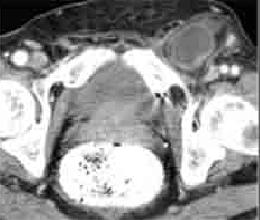

- Occlusion des hernies inguinales etranglees :

Aspect radiologique de occlusion des hernies etranglee est

image de l'obtacle se situe a la region inguino-scrotale (

hernie crurale ou hernie au dessus de arcade crurale ) , au

trous obturateurs ou a la ligne blanche + Image de

distention de l'intestin en amont de l'obtacle

| Hernie inguinale etranglee : Image TDM en

coupe axiale a travers L5 |

Hernie

inguinale etranglee : Meme cas en coupe axiale a

travers symphyse pulbienne |